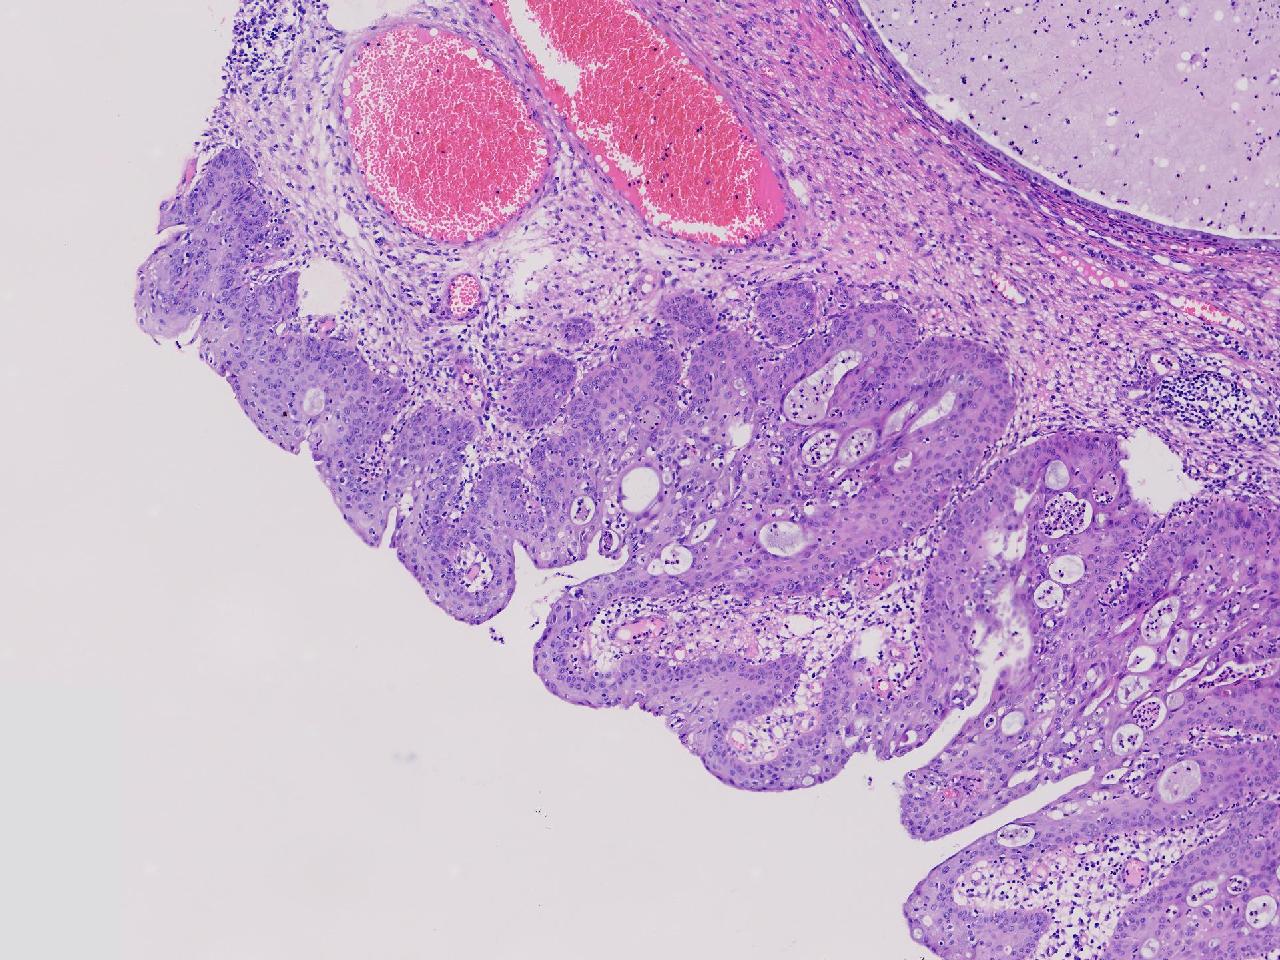

性别年龄42岁临床诊断宫颈赘生物

一般病史女,42岁,妇检时发现宫颈赘生物,大小0.2cmx0.5cm

标本名称管状赘生物

大体所见灰白色不整形软组织2块,一个直径0.3厘米,一个直径0.2厘米。

炎症

低级别诊断需要有个尺子,这个尺子就是“似是而非为非”,这个连似是而非都达不到。

有非典型鳞化,建议HPV检测

慢性宫颈炎伴腺上皮鳞化。